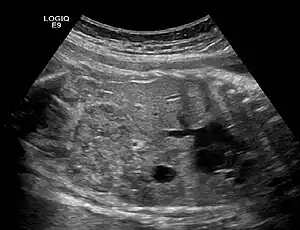

| Ectopic crossed fused kidney in a fetus approx. 34 weeks | |

Ectopic kidney describes a kidney that is not located in its usual position. It results from the kidney failing to ascend from its origin in the true pelvis or from a superiorly ascended kidney located in the thorax.[1]

a) Origin of the left renal artery from the aorta b) left renal artery entering the lower pole of the ectopic kidney